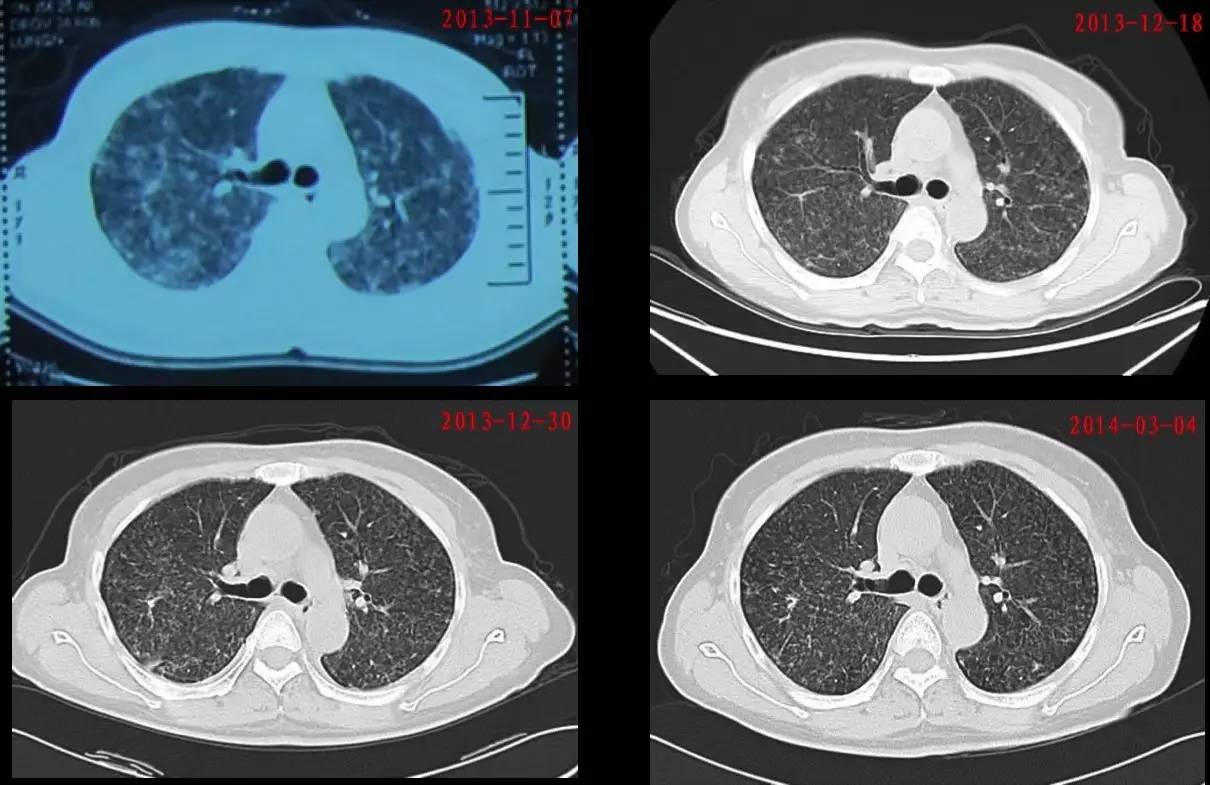

1. 胸部CT提示双肺病变较前吸收(图5)。

图 5:该患者治疗前后胸部CT对比

2. 血气分析示:PH 7.43,PaO2 85 mmHg,PaCO2 33 mmHg,BE -1.6 mmol/L,HCO3-23.7 mmol/L,P(A-a)O2 28 mmHg。

3. 肺功能:轻度限制性肺通气功能障碍,气道阻力正常,肺弥散功能轻度下降。